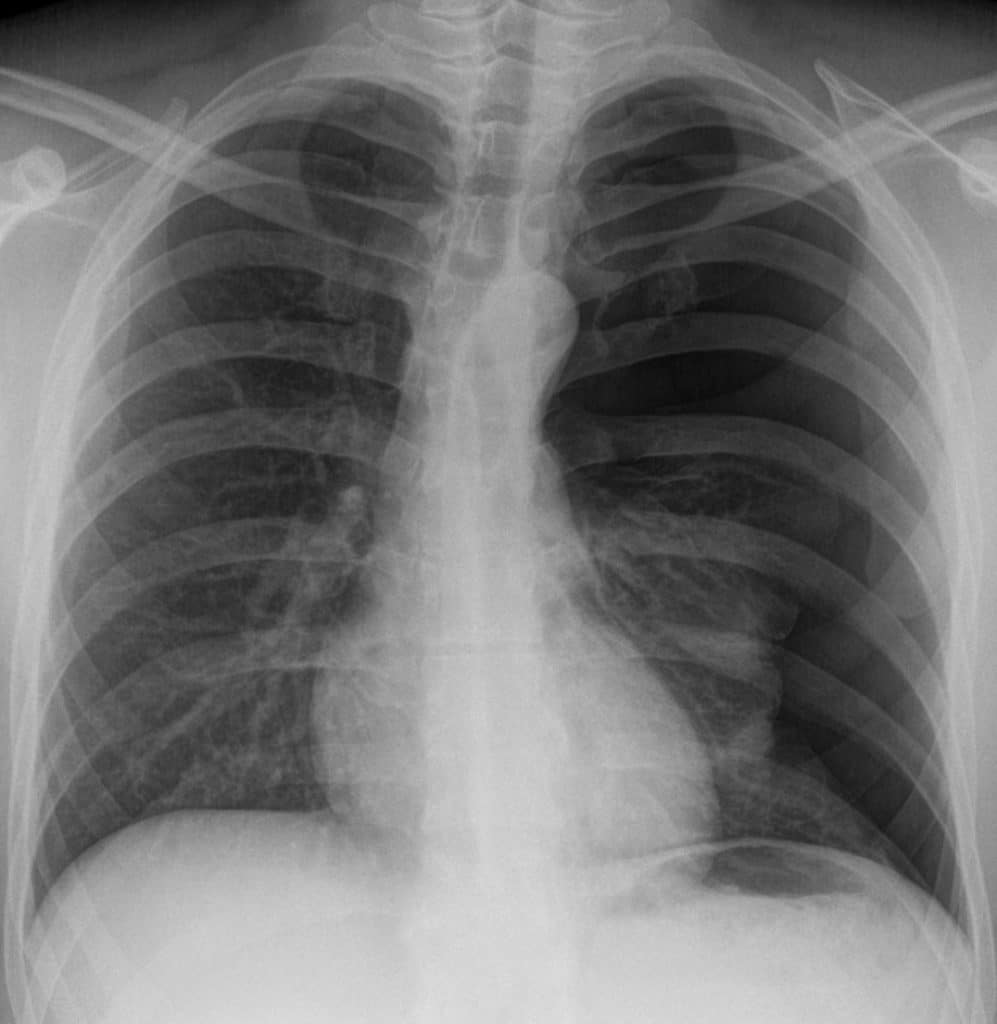

Pneumothorax

A pneumothorax (commonly referred to a collapsed lung) occurs when air or gas is present within the pleural space. This removes the surface tension of the serous fluid present in the space, reducing lung extension.

Clinical features include chest pain, and shortness of breath, and asymmetrical chest expansion. Upon percussion, the affected side may be hyper-resonant (due to excess air within the chest).

There are two main classes of pneumothorax – spontaneous and traumatic.

• Spontaneous: A spontaneous pneumothorax occurs without a specific cause. It is sub-divided into primary (no underlying respiratory disease) and secondary (underlying respiratory disease present).

• Traumatic: A traumatic pneumothorax occurs as a result of blunt or penetrating chest trauma, such as a rib fracture (often seen in road traffic collisions).

Treatment depends on identifying the underlying cause. Primary pneumothoraces tend to be small and generally require minimal intervention, whereas secondary and traumatic pneumothoraces may require decompression to remove the extra air/gas in order for the lung to reinflate (this is achieved via the insertion of a chest drain).

Fig 3

Radiographic appearance of a left pneumothorax.